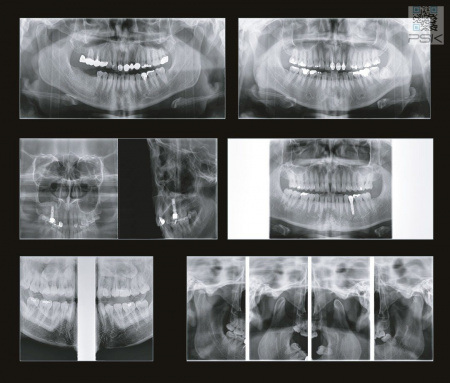

Области сканирования (FOV), см 3.5×4, 4×5, 7×7, 8×8, 16×8, 16×14

Виды исследований Панорама, КТ